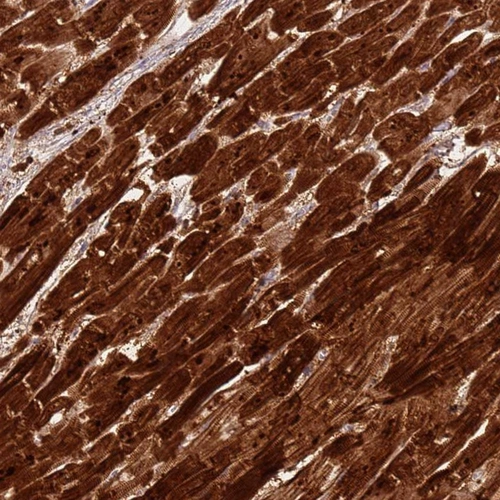

Immunohistochemistry analysis in human heart muscle and prostate tissues using Anti-CSRP3 antibody. Corresponding CSRP3 RNA-seq data are presented for the same tissues.